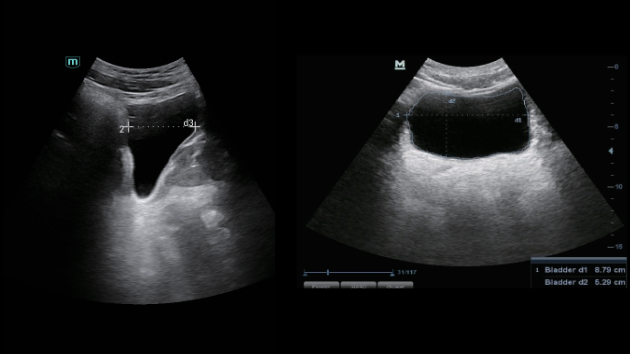

Soluzioni di diagnostica per immagini complete con tecnologia ZST+

La piattaforma ZST+ è un'innovazione straordinaria, che rappresenta un'evoluzione nel campo dell'ecografia. Grazie alla trasformazione delle metriche a ultrasuoni dal beamforming convenzionale all'elaborazione basata sui dati di canale, supera la tradizionale limitazione del trade-off tra risoluzione spaziale, risoluzione temporale e uniformità dei tessuti, offrendo una qualità d'immagine eccezionale per infinite soluzioni di imaging con miglioramenti continui.